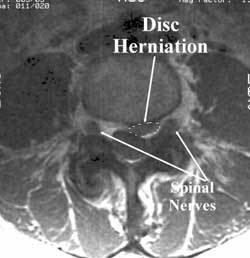

The spinal nerve on the left side of the picture is in the “neural foramen”–a canal or doorway for the nerve to leave the spinal canal and go out into the body.

Disc herniations, bone spurs from the vertebral body and bone spurs from the facet joints can press on the nerve in the neural foramen

In this patient, a fragment of the L4-5 disc has extruded outside its normal location and is pushing into the spinal canal.